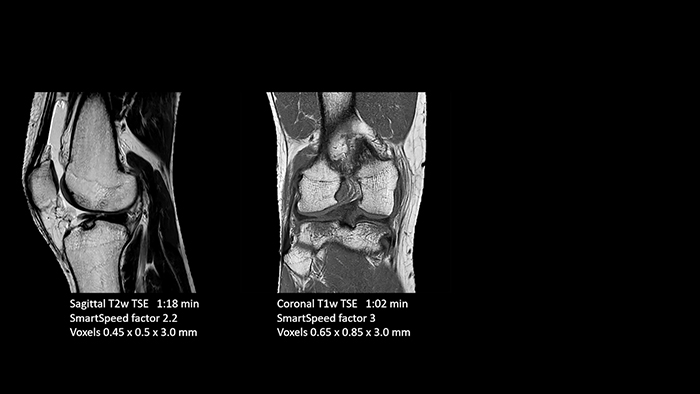

Previously, the practice wasn’t able to use 3D imaging on all joints, because the time required was too long, and on some joints it was simply not possible to achieve a good quality image, Dr. Schröter says. “Now, with SmartSpeed we consistently use 3D imaging for all joints and can thus discover the smallest changes, for example in the cartilage. And that, of course, helps us in making a detailed diagnosis.” Dr. Schröter says their MSK images show high contrast and extremely high quality. He mentions the menisci as an example. “We use a 3D proton density weighted fatsat sequence, thickness is 0.3 mm and scan time 3 minutes. The MPRs show an unbelievable resolution. Very small tears and even fraying of the tip of the meniscus become visible, which is normally only possible in arthroscopic surgery. When imaging the small joints of the fingers and the thumb we achieve extraordinary quality. Using SmartSpeed we succeed in displaying even very small structures anatomically correct, enabling us to see the extent of possible injuries. Tendons and ligaments appear with higher resolution so we can better see the injury pattern and describe and delimit it. Our referring physicians are fascinated by the extraordinary quality and high level of detail of the images. Patients are happy that the examination does not take too long. We hear from patients that it took a lot less time than they expected. This is especially important when scanning patients who are very uncomfortable in the MRI environment.”

SmartSpeed is used to reduce scan times. All three PDw orientations were obtained with only one 3D sequence using SmartSpeed. Performed with 1.5T Ambition X, 16ch dS Knee coil.